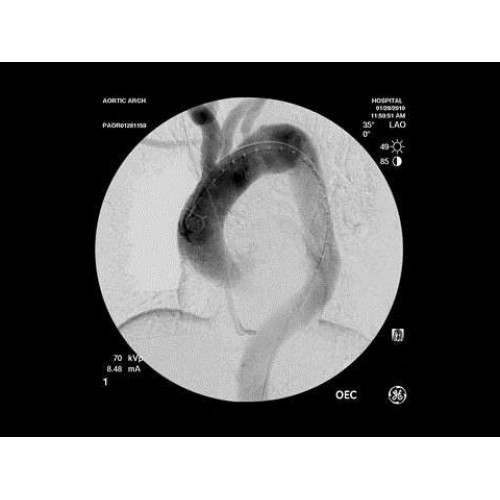

• Кардиохирургические вмешательства и ангиопластика

В операционной практике GE OEC 9900 Elite демонстрирует исключительную эффективность при проведении сложных малоинвазивных процедур. Оборудование позволяет значительно сократить время вмешательства и повысить его безопасность для пациента. Многие хирурги отмечают улучшение точности операций и комфорт работы с системой.

В ведущих медицинских центрах GE OEC 9900 Elite успешно применяется для проведения сложных кардиологических, нейрохирургических и ортопедических вмешательств. Система доказала свою эффективность при выполнении стентирования коронарных артерий, эмболизации сосудов головного мозга и вертебропластики. Многие учреждения отмечают повышение качества операций после внедрения этого оборудования.